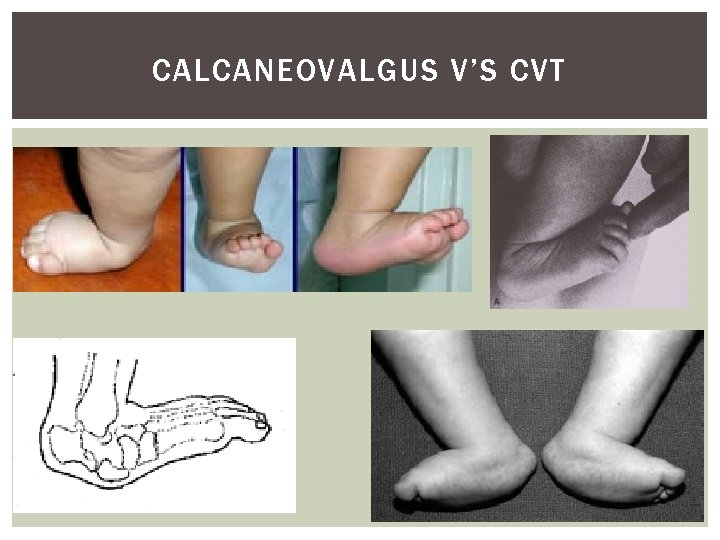

CALCANEOVALGUS V’S CVT